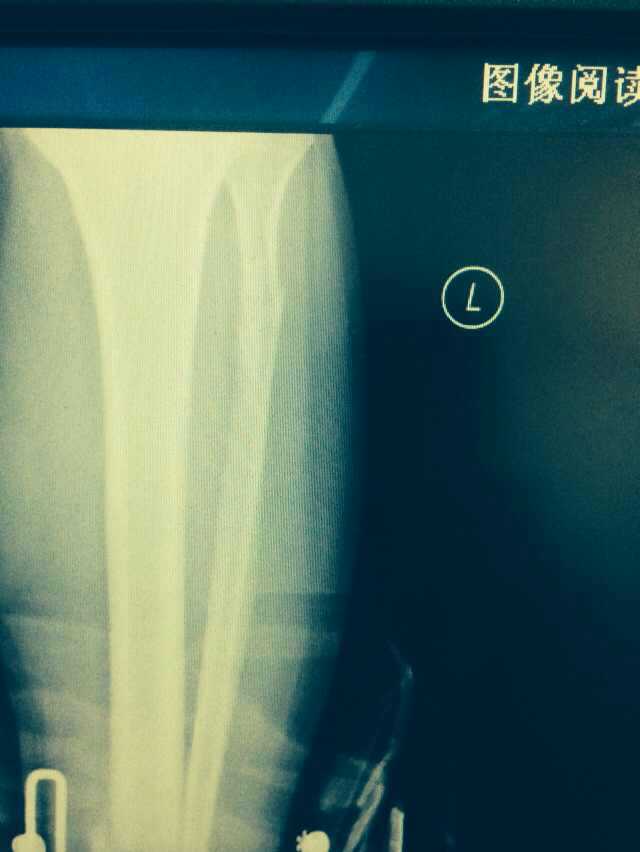

【byb.cn 】(來(lái)源:綜合)2014年12月18日,現(xiàn)年57歲的著名體育評(píng)論員韓喬生,在崇禮云頂滑雪場(chǎng),騎行德國(guó)雪上自行車(chē)的時(shí)候,因速度太快,控制不住,韓喬生為避免沖下路基,與一滑行單板的美女相撞,美女因裝備厚,無(wú)大礙,韓喬生則導(dǎo)致左腿脛骨、腓骨兩外骨折,后已經(jīng)被緊急送往北京的醫(yī)院治療。